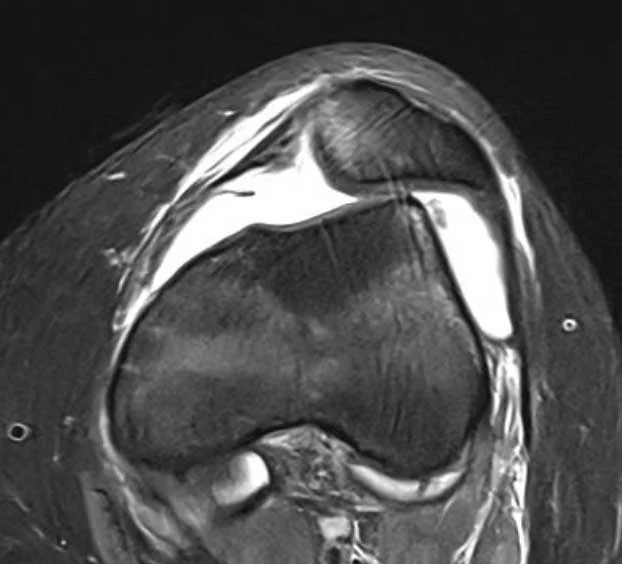

krankhaft veränderte Situation im Knie

Die korrekte Ausrichtung der Knochen ist dabei der wichtigste Faktor für die Stabilität der Kniescheibe und ihren gesunden Lauf in der Gleitrinne und sollte bei der Therapie vorrangig behandelt werden.

Häufig wird im Rahmen einer Kniescheibenverrenkung ein Riss des innenseitigen Kniescheibenhaltebandes („MPFL“) diagnostiziert. Abhängig von der Schwere der oben genannten Faktoren muss dieses nicht immer mitbehandelt werden. Dagegen sollten bei der Verrenkung entstandene Knorpelschäden, je nach Ausprägung, zeitnah mitbehandelt werden.